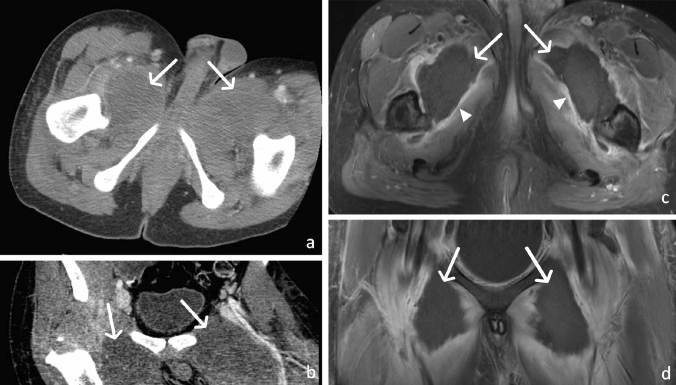

Given the large number of exiting spinal nerves in the abdomen and pelvis, peripheral nerve-sheath tumors are commonly encountered. Schwannomas and neurofibromas can be found anywhere along a peripheral nerve, and these two histologically distinct tumors share many imaging features. These tumors are usually less than 5 cm in diameter and on MRI have slightly greater signal than muscle on T1W images and exhibit high signal on T2W images. The “target sign,” where the center of the tumor is low in signal on T2W images with a peripheral rim of a high signal, is most often seen with neurofibromas (Fig. 8). Histologically, a central fibro-collagenous core and surrounding myxomatous tissue account for this imaging pattern. The target sign may also be seen in schwannomas; however, in these lesions, it is due to a central distribution of the more cellular Antoni type A cells, with a surrounding rim of hypocellular Antoni type B cells. Loss of a previously seen target sign in a peripheral nerve sheath tumor is concerning for malignant transformation. The tumor sometimes appears to have a “tail” on either side, representing the entering and exiting nerve [15, 16]. While these are benign tumors, they may exhibit locoregional mass effect and may show heterogeneous enhancement (Fig. 9).

Fig. 8.

36-year-old male with Neurofibromatosis type I demonstrating a penile and multiple additional sacral neurofibromas. Sagittal (a) and coronal (b) T2W fat-saturated MR images demonstrate an elongated mass with high signal intensity in the dorsal aspect of the penis (arrow). Axial (c) T2W fat-saturated images reveal additional ovoid masses of the sacral plexus which demonstrate the “target sign” appearance, with high peripheral signal intensity and low central intensity (arrow)